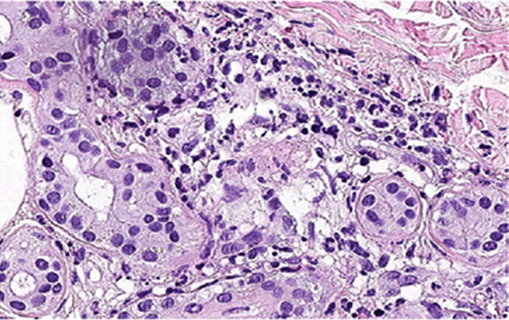

Punch biopsy of the skin revealed PNN-rich inflammatory dermal lesions surrounding apocrine (sweat) glands, which were consistent with NEH (Figure 2) (Figure 3). No vasculitis was observed. The epidermis was normal.

Figure 2: (A, B) Neutrophilic infiltration around eccrine glands (H&E stain, (A: x50, B: x100).

Figure 3: Neutrophils surrounding and infiltrating the sweat gland epithelium with gland atrophy (H&E stain, x400).

The diagnosis is established by the detection of neutrophilic infiltration around eccrine glands with necrosis in biopsy samples. Some non-specific epidermal changes may also be present, such as spongiosis, isolated keratinocyte necrosis, and vacuolization of the basal layer.